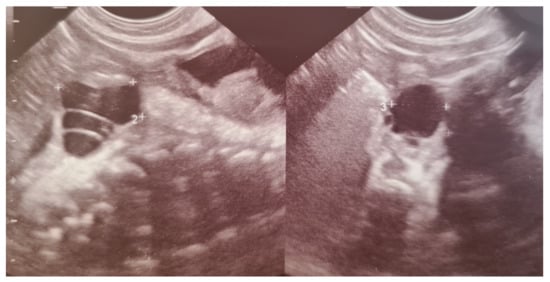

Ovarian cysts usually arise from mature follicles and are the most common abdominal cysts in female fetuses and newborn girls [34,35]. They result from fetal exposure to maternal and fetal gonadotropins and are found more often in newborns whose mothers had increased levels of human chorionic gonadotropin – hCG (diabetes, maternal isoimmunization). Most of them are detected prenatally [34,35]. Ultrasonography is the imaging technique of choice for diagnosing ovarian cysts, as it makes it possible to differentiate them from other cystic lesions. Most ovarian cysts are functional, benign follicular cysts that do not interfere with the course of pregnancy or birth. They can be divided into simple or uncomplicated—completely anechoic, homogenous, and thin-walled—and complex or complicated—characterized by fluid-debris level and a thick echogenic wall, which may contain solid components, clot, or septa (Figure 3). In infants, complex cysts are most consistent with ovarian torsion that occurred prenatally. Frequently, even complex cysts regress after birth, as maternal hormone stimulation decreases [35,36,37].

Figure 3. Simple and complex ovarian cysts in a premature newborn girl. The complex cyst contains septa.